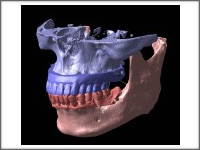

研究用模型の合成

研究用模型とCTデータを合成することで金属アーティファクトのないクリアな3D画像を実現します。

顎模型(石膏)

iCATで模型合成した3Dデータから石膏積層により作製する顎模型は、骨の状態・歯牙の形状をクリアに再現。 金属アーティファクトのないリアルな模型は手術前のイメージ確認やインフォームド・コンセントに有効です。 iCATで模型合成した3Dデータから石膏積層により作製する顎模型は、骨の状態・歯牙の形状をクリアに再現。 金属アーティファクトのないリアルな模型は手術前のイメージ確認やインフォームド・コンセントに有効です。